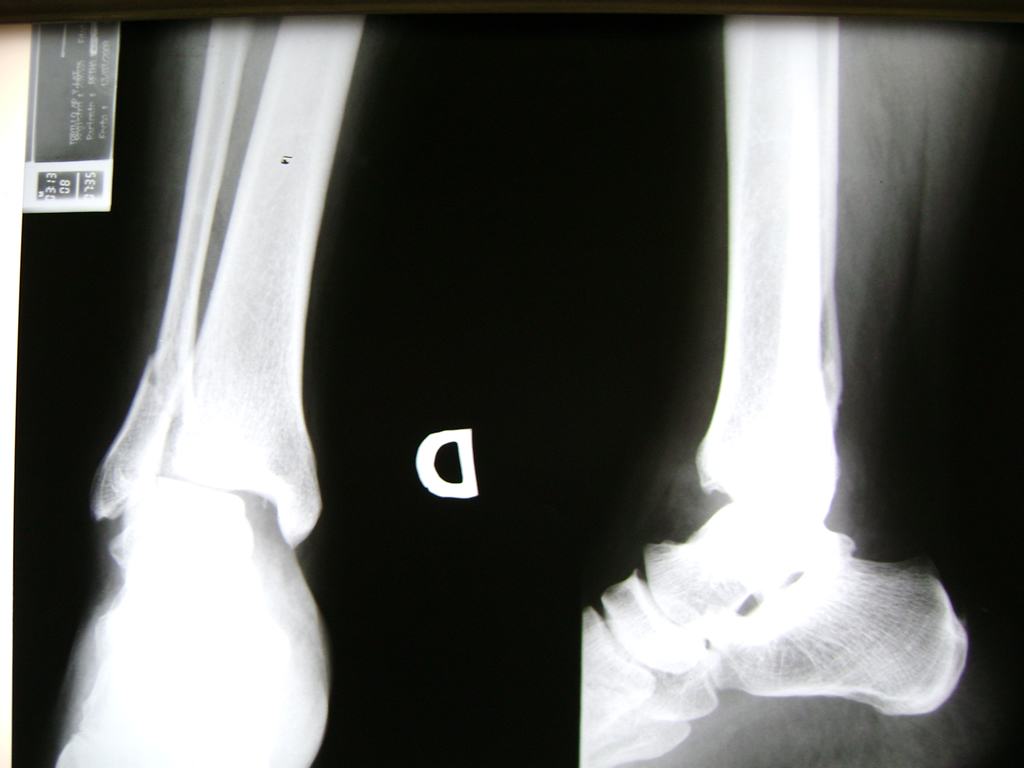

Una fractura de tobillo es la rotura de uno o más de los huesos del tobillo. Estas fracturas pueden ser:

- Producirse en uno o ambos lados del tobillo.

- Los extremos de los huesos están desalineados entre sí (desplazados).

- La fractura se extiende hasta la articulación del tobillo (fractura intra-articular).